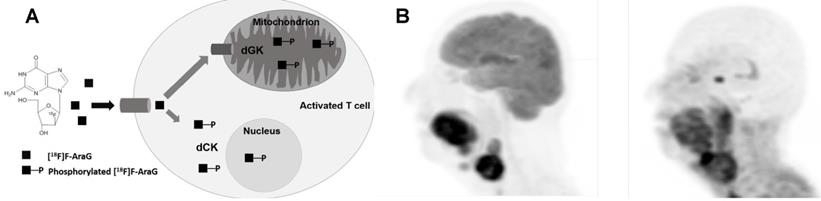

Figure 1

(A) Mechanism of uptake of 18F-ARAG: Reproduced from Levi J et al. CCR (doi:10.1158/0008-5472.CAN-19-0267). (B) Patient with head and neck carcinoma. PET/CT imaging with 18F-FDG and 18F-ARAG shows prominent uptake in the lesions in larynx; uptake is also noted in 18F-ARAG scan with heterogenous uptake. (Courtesy: Drs. Colevas, Sunwoo, and Davidzon, Stanford University) (Reprinted with permission from Elsevier, Pandit-Taskar N, Postow MA. Immune-Directed Molecular Imaging Biomarkers. Semin Nucl Med. 2020 Nov;50(6):584-603. doi: 10.1053/j.semnuclmed.2020.06.005. Epub 2020 Jul 15. PMID: 33059826.)

To overcome this issue, 9-(β-D-Arabinofuranosyl) guanine (AraG), a non-catabolizible imaging agent, was developed. As a guanosine analog, it can be phosphorylated by dCK and, consequently, trapped intracellularly in T cells in vivo without any toxicity [10, 11], therefore serving as an ideal targeted small molecule PET imaging tracer (Figure 1). In a murine model of colorectal cancer, two days post-administration of anti-PD-1 treatment, responder mice showed a significantly higher 18F-AraG PET signal in their tumors relative to a non-responder mice, indicating 18F-AraG PET was able to successfully predict the response to programmed death-1 (PD-1) blockade [11]. In patients, 18F-AraG preferentially accumulates in activated CD8+ T cells with about 7 times higher uptake in activated T cells as compared to murine cells [10]. Currently, four phase I (NCT04524195, NCT04052412, NCT04678440, NCT04186988) and two phase II (NCT04726215, NCT04260256) human studies are underway to study biodistribution and kinetics in patients with non-small cell lung cancer (NSCLC) treated with checkpoint blockade.